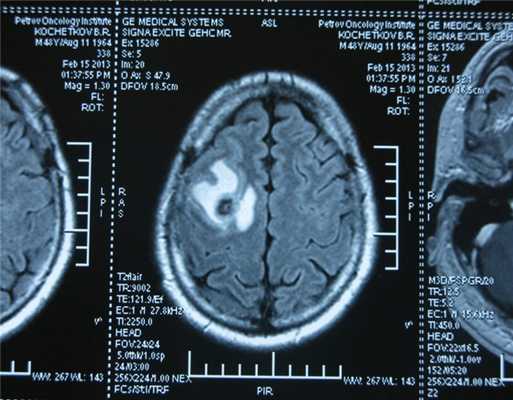

Головной мозг

Герминогенные новообразования в данной области - это примерно 2-4% от всех внутричерепных (интракраниальных). Патология в 75% случаев диагностируется у мальчиков, за исключением турецкого седла, где новообразования в основном локализуются у девочек.

Герминомы формируют инфильтрирующие опухоли больших размеров, часто являющиеся источниками субарахноидальных (между мягкой и паутинной оболочками мозга) и вентрикулярных (желудочковых) метастаз.

Рисунок 7. - Герминома головного мозга.

Рисунок 9. - метастаз в головной мозг при герминогенной опухоли.

Также выполняют МРТ головного мозга, чтобы выявить наличие метастазов в нем.

![Метастаз в головной мозг при герминогенных опухолях (МРТ головного мозга)]()

Метастаз в головной мозг при герминогенных опухолях (МРТ головного мозга)